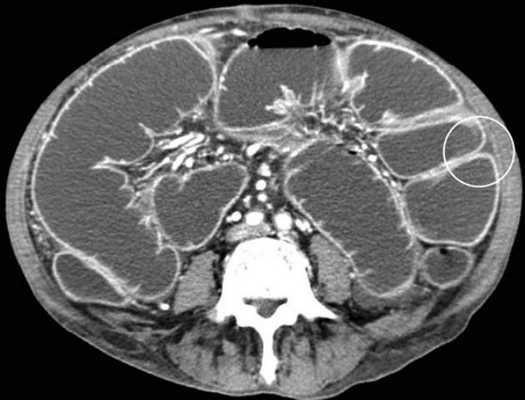

Мальротация кишечника (нонротация) у мужчины 39 лет.

(а, б) Тощая кишка — прямое продолжение двенадцатиперстной (стрелка, а), отсутствуют нормальные 3-й и 4-й сегменты двенадцатиперстной кишки, а также двенадцатиперстно-тощекишечный переход (звездочка, б).

(в, г) Петли тонкой кишки (прямые стрелки) лежат в левой половине брюшной полости, а ободочная кишка (изогнутые стрелки) — в правой половине. Заворот средней кишки у мальчика 11 лет.

Врожденная мальротация кишечника обусловлена нарушением нормальной ротации первичной кишки в направлении против часовой стрелки. Среди широкого разнообразия вариантов мальротации в клинической практике наиболее часто встречают полное отсутствие ротации (нонротация). При этом состоянии тощая кишка служит прямым продолжением двенадцатиперстной, при этом отсутствуют 3-й и 4-й сегменты двенадцатиперстной кишки и двенадцатиперстно-тощекишечный переход. Петли тонкой кишки лежат в левой половине брюшной полости, а ободочная кишка — в правой половине. При завороте средней кишки ножка брыжейки сужена, а двенадцатиперстно-тощекишечный переход (местонахождение связки Трейтца) чаще расположен низко, по правую сторону от средней линии. Такие условия приводят к перекручиванию неправильно фиксированной тонкой кишки, а верхние брыжеечные артерия и вена располагаются в короткой и суженной ножке брыжейки.